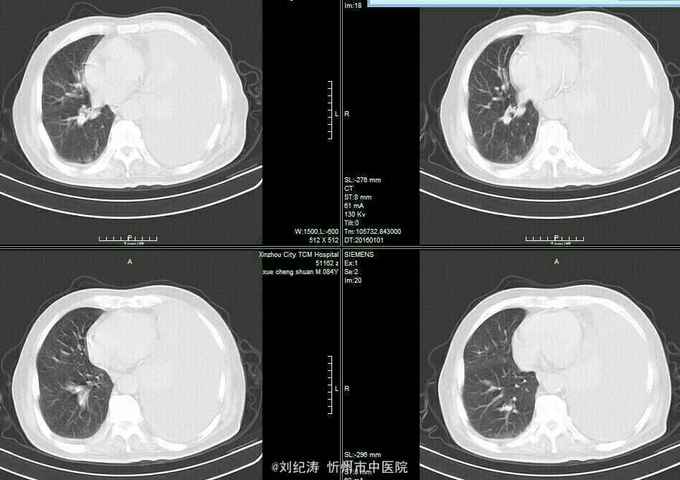

查体:ECOG评分:3分,生命指征平稳,浅表淋巴结未触及明显肿大,双眼睑无水肿,唇无发绀,颈软,双侧胸廓对称,左肺语颤增强,左肺呼吸音消失,右肺呼吸音粗,可闻及哮鸣音,心律齐,腹平软,肝脾肋下未触及,移动性浊音阴性,肠鸣音3次/分,双下肢无水肿。 辅助检查:血常规(2016.1.1):WBC:10.6*109/L,RBC:4.69*1012/L, PLT:165*109/L ,HGB:167g/L.生化(2016.1.1):谷丙转氨酶11U/L,谷草转氨酶11U/L,总蛋白60g/L,白蛋白33g/L,尿素:9.8mmol/L,肌酐:123umol/L,尿酸:251 umol/L,血糖:7.37 mmol/L;电解质:钾:4.79mmol/L,钠:123.5 mmol/L,氯:85.7 mmol/L,钙:2.03 mmol/L。肺部CT(2016.1.1):左肺完全萎缩,左侧胸腔大量积液,右肺未见异常,纵膈轻度右移,未见明显肿大淋巴结。